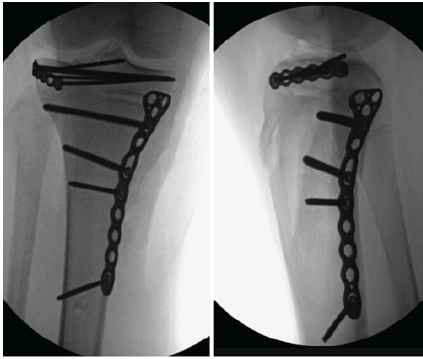

On post-injury day 8, the patient returned for removal of external fixator and definitive fixation. The medial side was addressed first through a posteromedial approach. After direct open reduction, a small fragment plate was used to buttress the medial condyle with all fixation performed distal to the physis. Attention was then turned to the lateral side where a standard anterolateral approach was made, centered over Gerdy’s tubercle. A femoral distractor was applied for lateral joint visualization and a submeniscal arthrotomy was performed. The flipped articular fragment was noted to be trapped between the femur and the tibia. When this piece was rotated anteriorly, the torn lateral meniscus was revealed and noted to be impacted into the tibial metaphysis. The articular fragment was reduced and held with Steinmann pins. A minifragment plate was then contoured as a rim plate and screws were inserted to raft and secure the articular fragment as well as the medial epiphysis. All lateral fixation was proximal to the physis (Fig. 3). The lateral meniscus was then repaired using an all-inside device posteriorly and open repair to the lateral plate for the remainder of the body. Following fixation, the knee was ligamentously stable on examination.

Figure 3: Final intraoperative fluoroscopic images following fixation: All lateral fixation was kept proximal to the physis and all medial fixation distal to the physis.